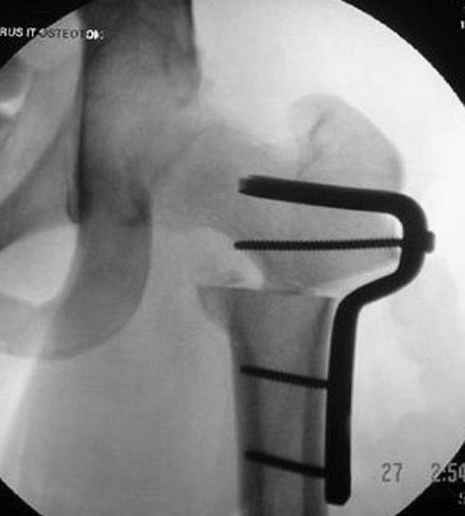

Несколько снимков из моей коллекции, чтобы разьяснить, почему мы до сих пор делаем различные варианты остеотомии.

На рисунке N1 предоперационный план лечения ложного сустава шейки бедра- линия ложного сустава, угол и направление введения импланта, клиновидная остеотомия в градусах и миллиметрах, второй снимок после коррекции, расчет, на сколько удлиняется конечность и размеры импланта;

N3 рисунок окончательный снимок, после операции моя рентгенограмма должен выглядеть примерно как эта картина. На N4 снимке клин перед удалением; N5 послеоперации 3 нед.; N6 окончательная рентгенограмма.

Djoldas Kuldjanov 23 Ноябрь 2004, 18:21

пластическая модель; и коррекция бедра аппаратом Илизарова.